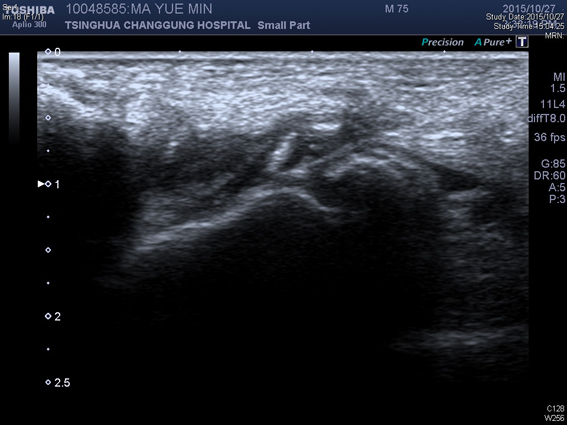

踝关节超声提示:右踝关节边缘可见少量骨质增生,外侧可见局部软组织水肿增厚。

超声引导右侧踝关节腔内PRP注射